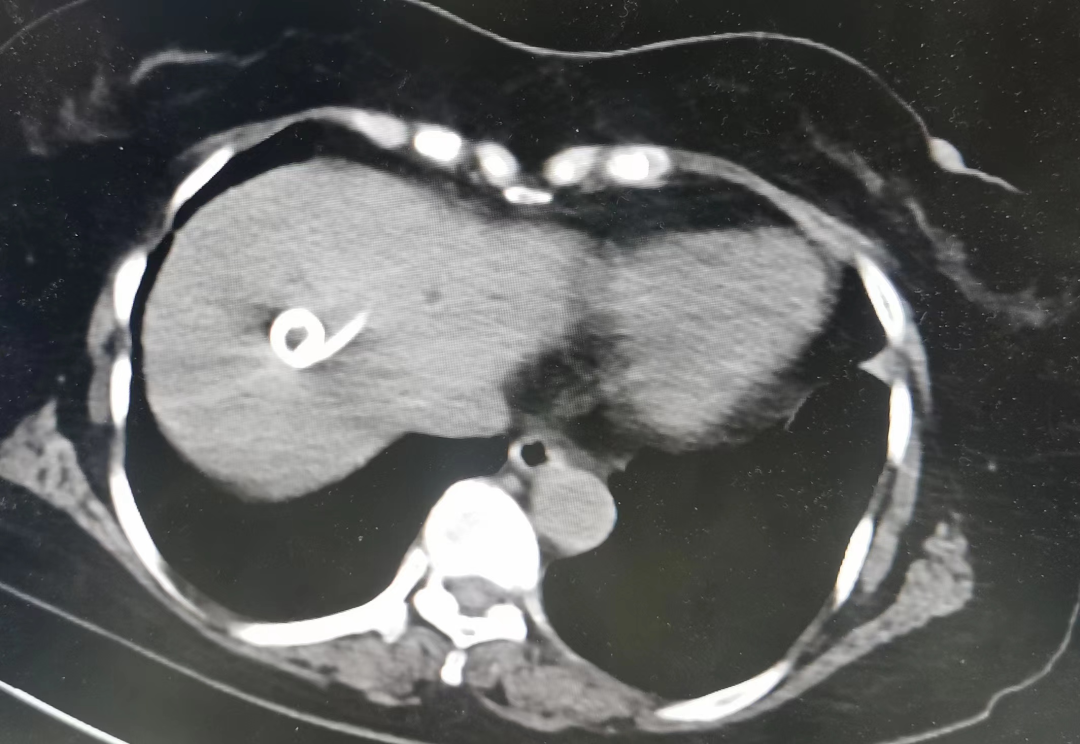

图2.CT引导手术操作

结合患者病情进展情况,考虑肝脏大囊肿并囊内出血可能,经科内专家讨论后,决定分步进行:先由内镜中心行无痛胃肠镜检查,消除门脉高压、食管胃底静脉曲张及胃肠息肉等病变。经检查,发现患者存在慢性萎缩性胃炎、幽门螺旋杆菌感染。予以内科治疗。第二步,联合介入室在CT引导下经皮经肝肝囊肿穿着置管引流术及无水酒精硬化术。术后症状明显好转,穿刺后共引流出500ml液体。留置引流管引流,待引流液明显减少、复查CT提示囊肿囊壁塌陷后再次行无水酒精注射硬化剂硬化治疗。